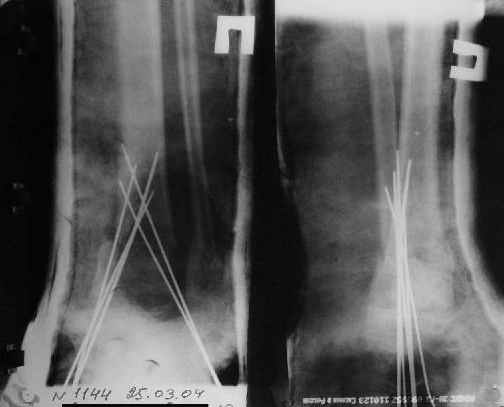

A>> Скелетное вытяжение за пяточную кость.

A>> Спицы удалены через 1,5 недели после операции.

A>> Особого смысла в них не было.

AVM> Не было. Можно было, если особенно хотелось, провести одну

AVM> интрамедулярно...

Но только смысла не имело. Подвижности небыло. Рубцы хорошо держат.

Вытяжение